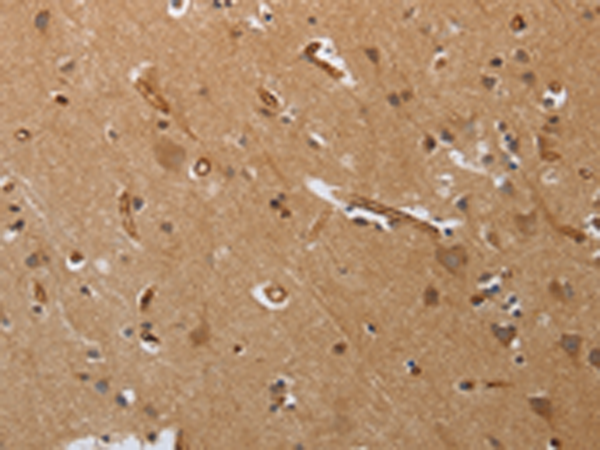

分类: 科研抗体货号: P11338别名: NaN; SNS-2; NAV1.9; SCN12A应用: IHC反应种属: Human, Mouse, Rat